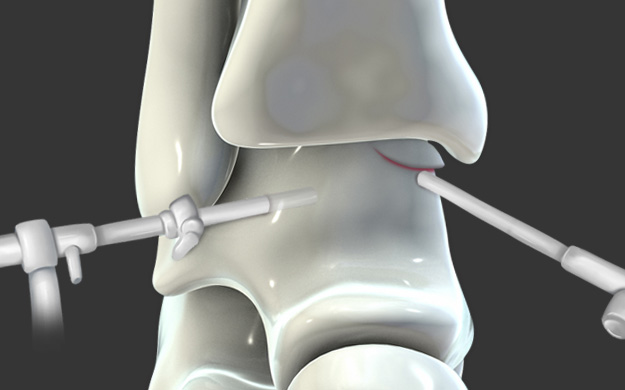

관절경을 통하여 손상된 연골 부위를 정리하고 뼈에 작은 구멍을

여러 개 뚫어서 연골 재생을 유도하는 방법입니다.

섬유성 연골로 재생되나 미세 천공술 단독으로도

특히 발목에는 효과가 좋습니다.

연골 손상이 있는 부위에 작은 구멍을 여러 개 내준 후, 골수에서부터 좋은 피가 잘 올라오는 것을 확인합니다.

연골 재생술을 같이 하는 것이 계획되었다면 콜라겐 혹은 줄기 세포로 결손부위를 도포해줍니다.

거골의 내측부 연골 병변에 대해서 관절경을 통해 미세천공술과 콜라겐 주입술을 시행하였으며,

수술 5개월째 결손 부위에 연골이 잘 생성되어 있는 소견이 관찰되었습니다.